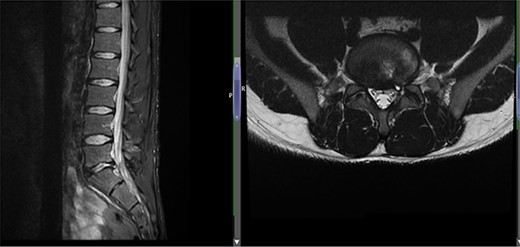

(A) Case 4—an initial MRI showing multilevel degenerative disc disease and a cyst at the lumbar L5/S1 which is causing impingement on the left S1 nerve root, and (B) case 4—comparison was made with the previous MRI; post-contrast scan shows that the L5-S1 left-sided cystic features have nearly diminished; no neoplastic lesion is detectable.